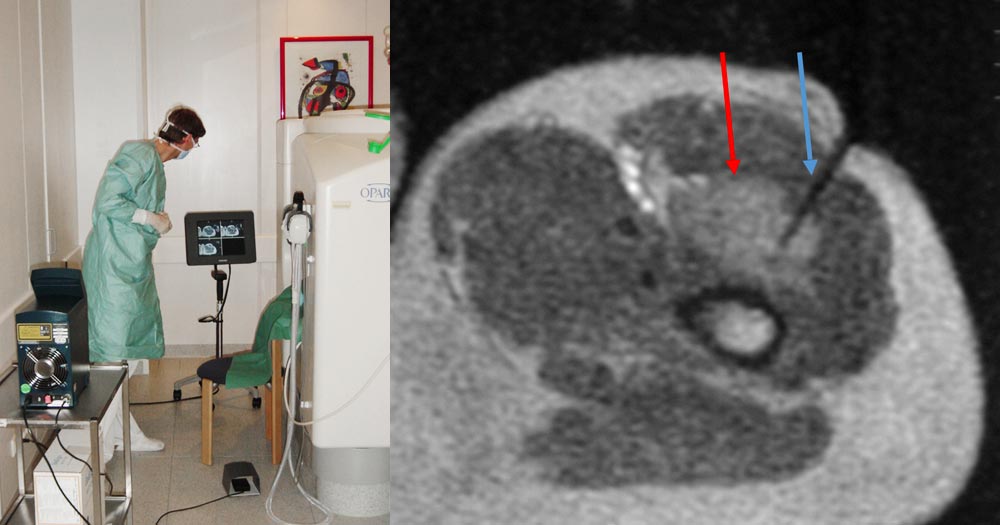

Endovascular laser applications (e.g., using the Nd:YAG 1064 nm or diode laser 810 nm) have successfully been used to treat dysplastic, tubular, epifascial, and subfascial venous malformations and marginal veins. The laser fiber is advanced into the vessel itself under sonographic, fluoroscopic or MRI guidance, and thermal coagulation occurs by delivery of laser light.

In interstitial laser application, the laser fiber is introduced through a puncture cannula into the target lesion, which is usually located deeper in the tissue, and thus this tissue is heated in the depth around the light emission area of the laser fiber. During retraction of the laser fiber, several applications are performed by pulling back a Nd:YAG laser (1064 nm) in a bare-fiber technique (direct frontal light emission from the laser fiber tip).